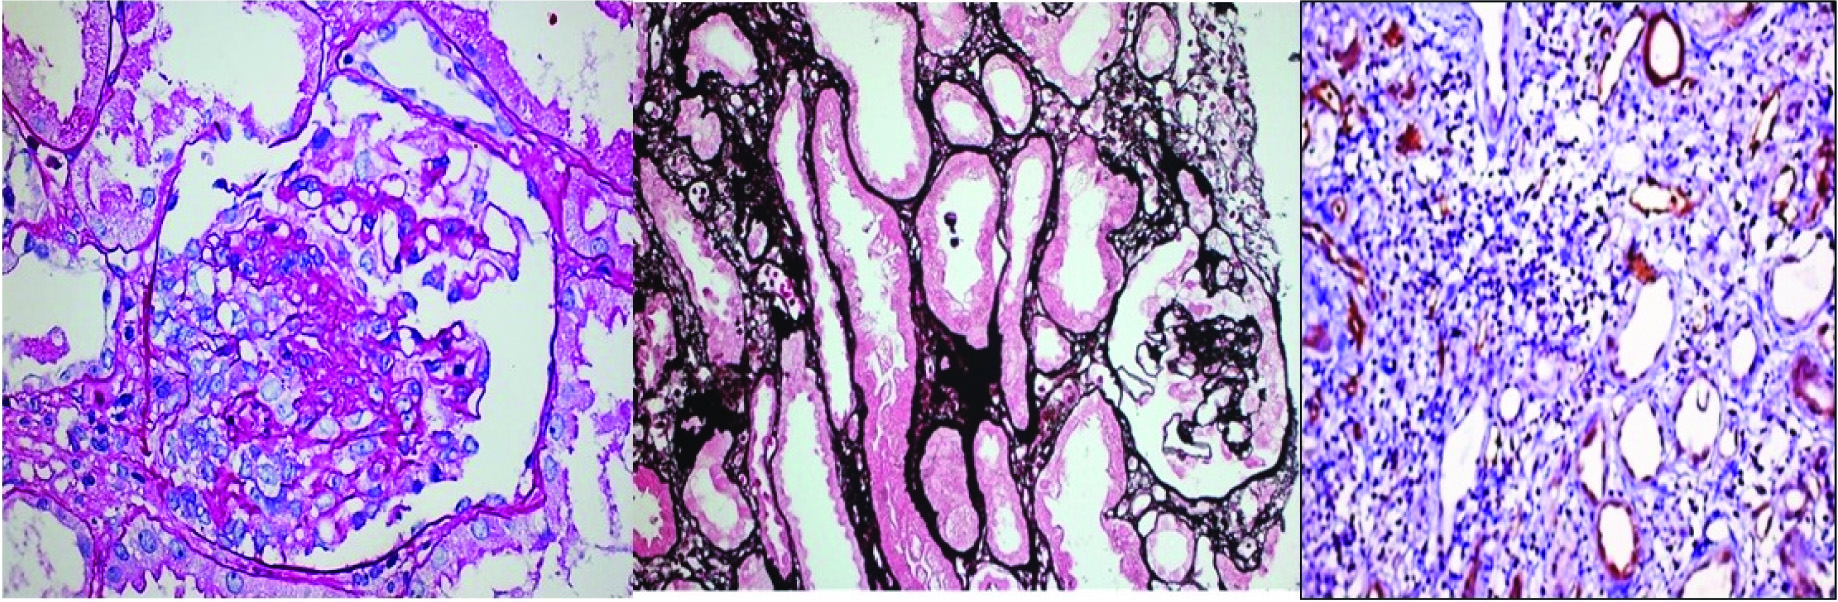

Collapsing glomerulopathy: Segmental and global collapse of glomerular capillaries, wrinkling and retraction of the glomerular basement membrane and marked hypertrophy and hyperplasia of podocytes [Table/Fig-1a-c].

De novo collapsing glomerulopathy with acute T+B cell mediated rejection; a) PAS 40X; b) Jone’s methanamine silver 20X; c) C4d, 20X. (Images from left to right)